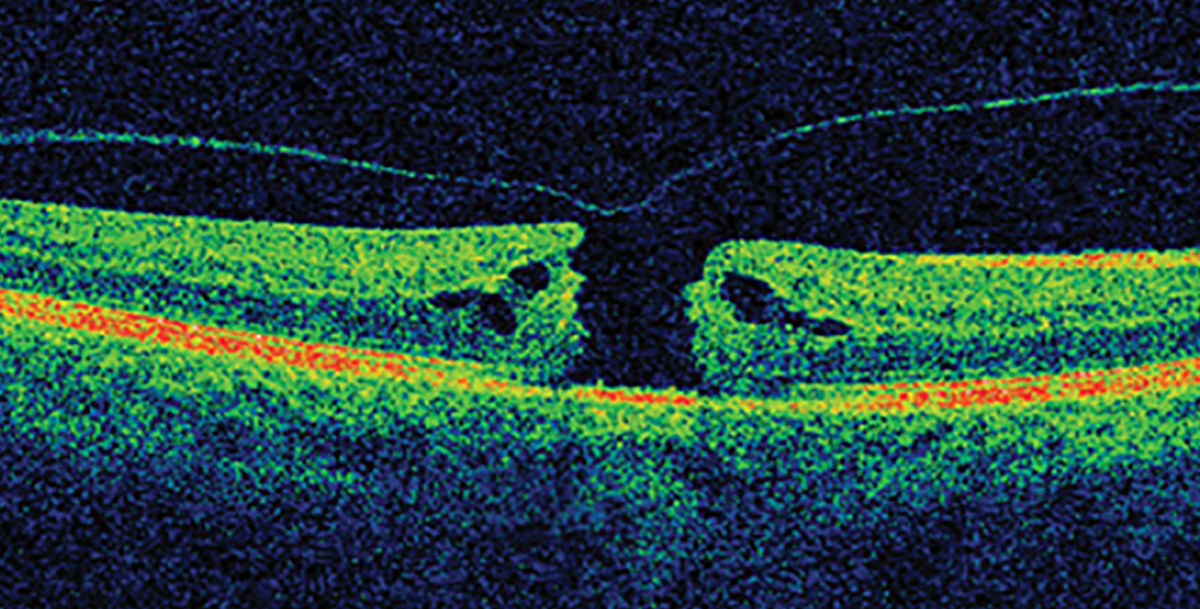

Dimitra Skondra MD PhD University of Chicago We have a big study regarding macular hole repair. A macular hole is a very common disorder affecting older patients that may already have macular degeneration. Surgery would be needed to repair the…